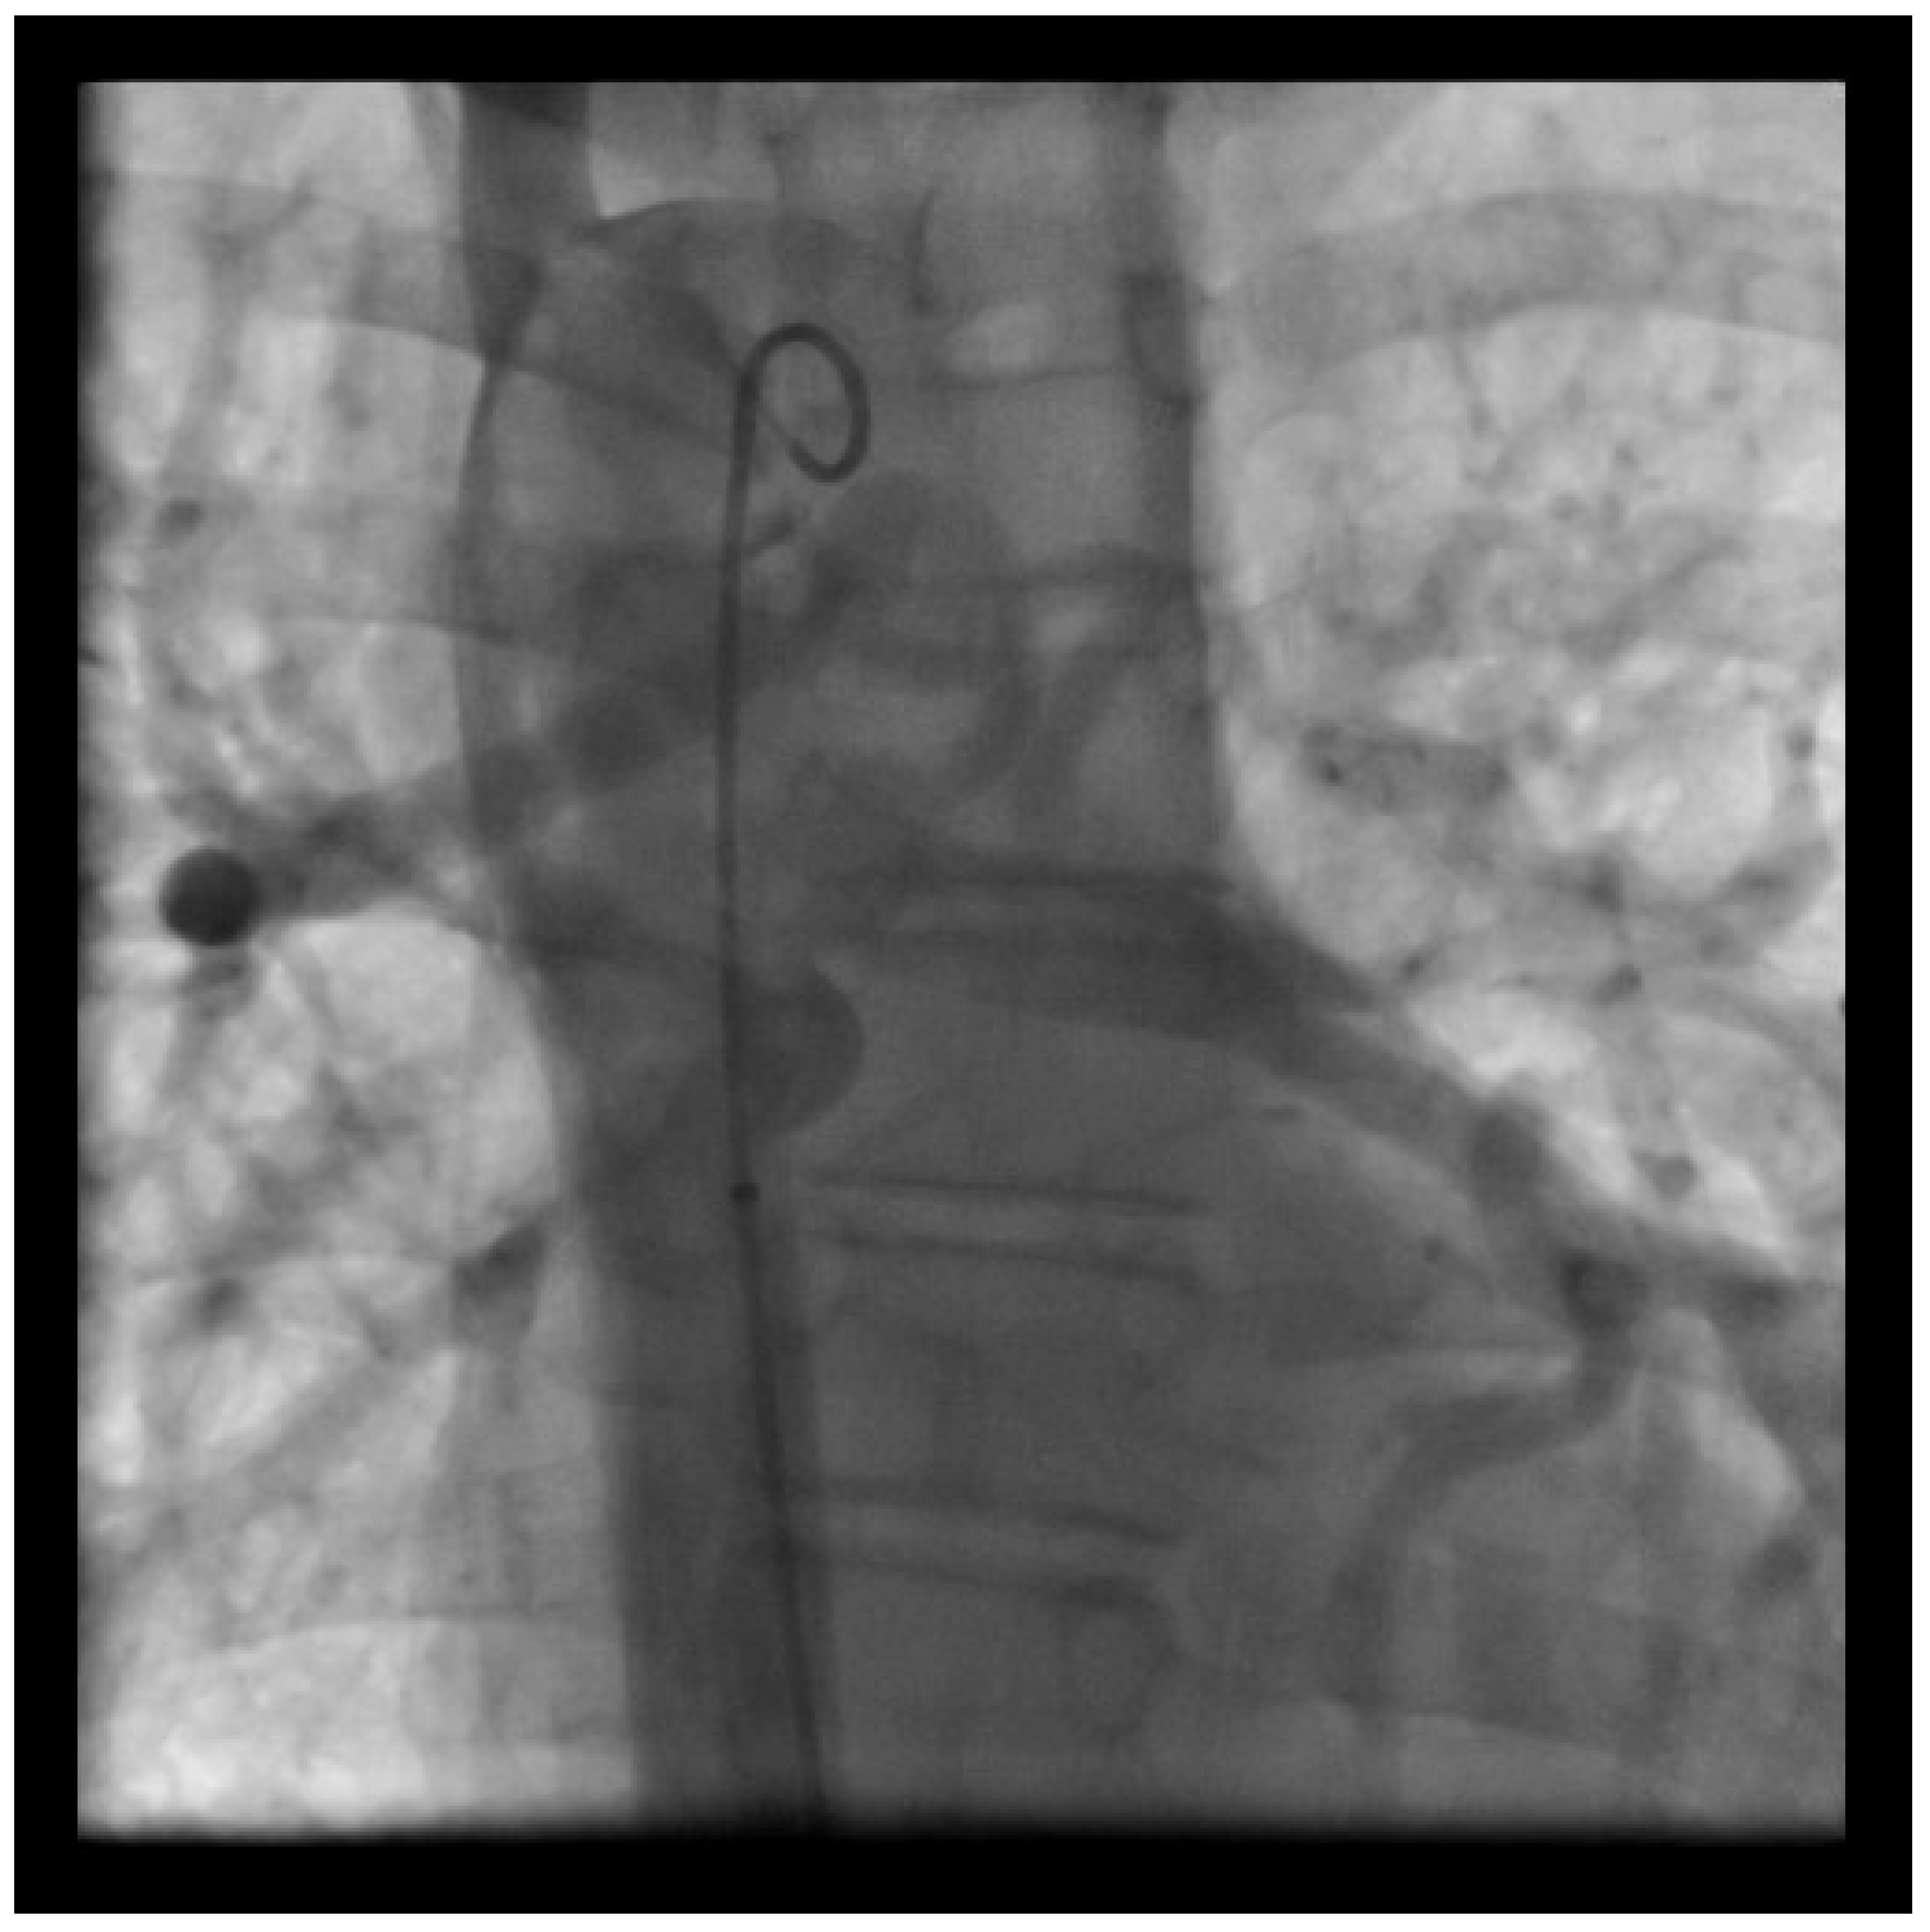

Figure 2.

Fifteen-year-old male with Pulmonary Atresia with VSD and MAPCAs (major aortopulmonary collateral arteries) and absence of native pulmonary arteries. Angiogram of descending aorta showing several MAPCAs deriving from the descending aorta, segmental pulmonary perfusion, stenosis to the right lower lobe, pulmonary hypertensive vessels to the left lower lobe.